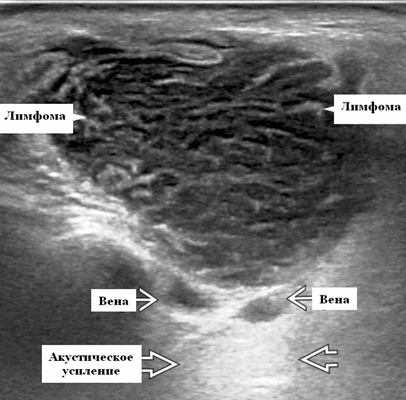

Серошкальное УЗИ. Узловая НХЛ. Одиночные или множественные увеличенные яйцевидные внутрипаротидные лимфатические узлы. Гомогенно гипоэхогенный по отношению к паренхиме околоушной железы. Сетчатый эхосигнал. Заднее акустическое усиление. Первичная паренхиматозная НХЛ. Рассеянный, неоднородный эхосигнал; нечеткие, гипоэхогенные, похожие на опухоль участки. В пунктате внутрикистозная или паренхиматозная кальцификация из-за конечной стадии воспалительного изменения. Небольшие кистозные области образуются из-за сдавления терминальных протоков лимфоидной гипертрофией. Множественные небольшие гипоэхогенные участки (представляют собой лимфоидные агрегаты), разбросанные на фоне ткани слюнной железы. Изменения могут имитировать хронический сиалоаденит и диагноз часто ставится при биопсии. На УЗИ необходимо искать аналогичное поражение других слюнных и слезных желез, фон синдром Шегрена, BLEL. Может иметь или не иметь перипаротидную и шейную лимфаденопатию

Цветной допплер. Узловая НХЛ. Выраженная центральная или внутриузловая гиперваскуляризация. Паренхима при неходжкинской лимфоме более диффузная железистая гиперваскуляризация. Васкуляризация от умеренной до выраженной в плохо очерченных образованиях.